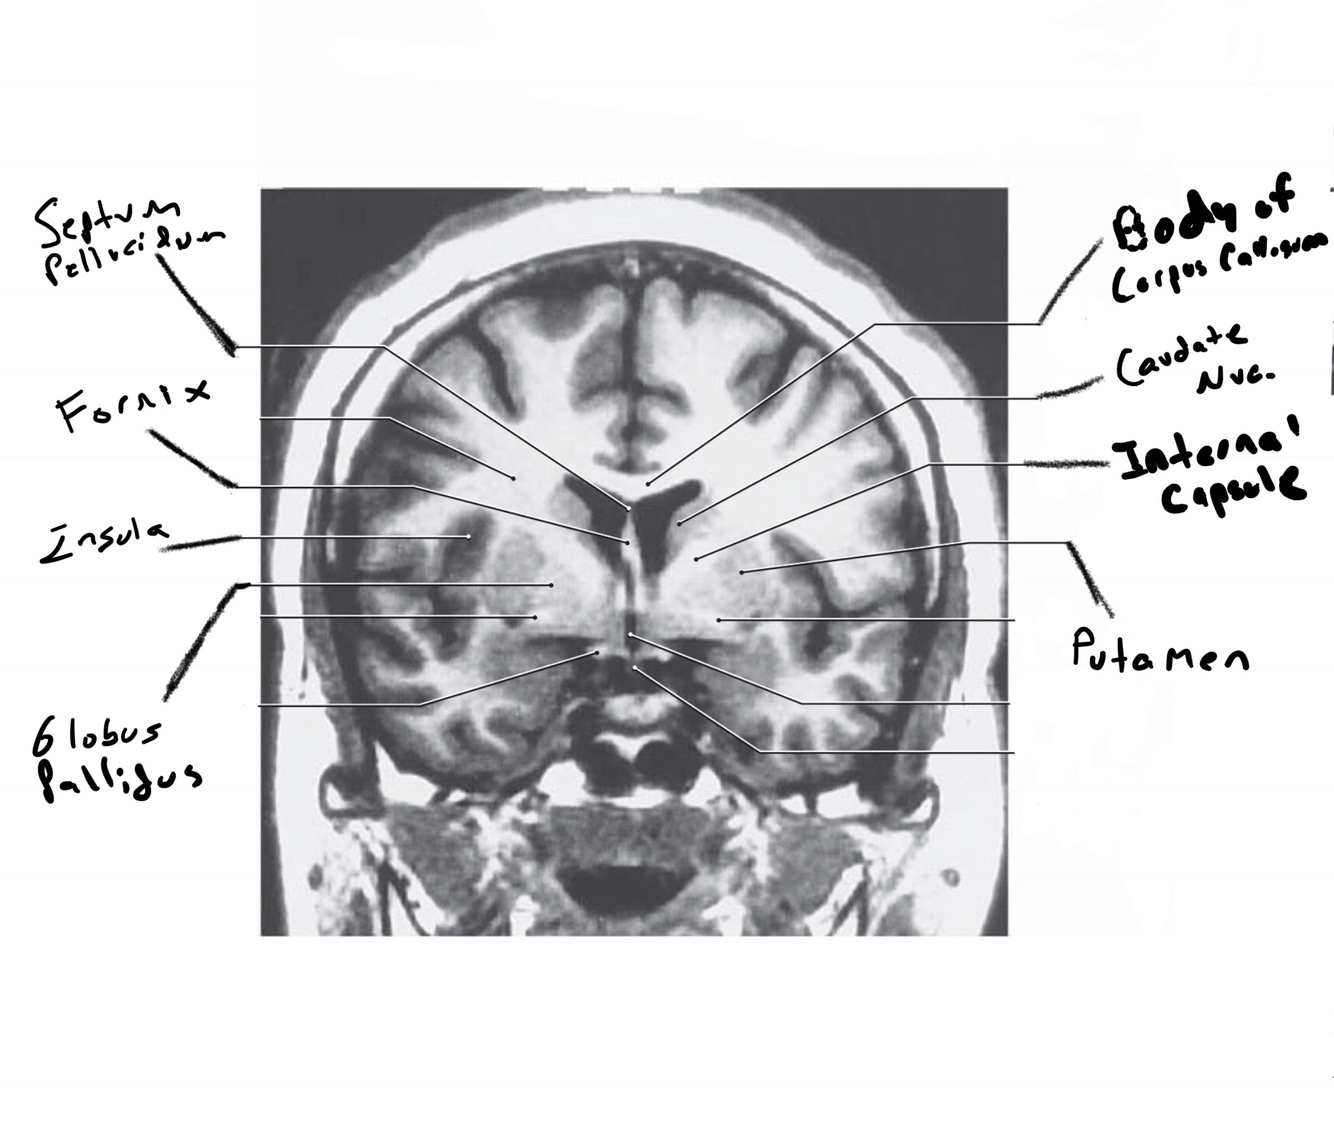

The structure indicated by the red line is? BONUS: SYMPTOMS IF THERE IS A LESION

motor spatial and directed movements (role in parkinsons?)

Bonus: Split Brain. L and R can’t communicate. Remember the test he did in class where he made us wave? Diagnose like that b/c wernickes is on left side so you cant wave ur left

motor problems